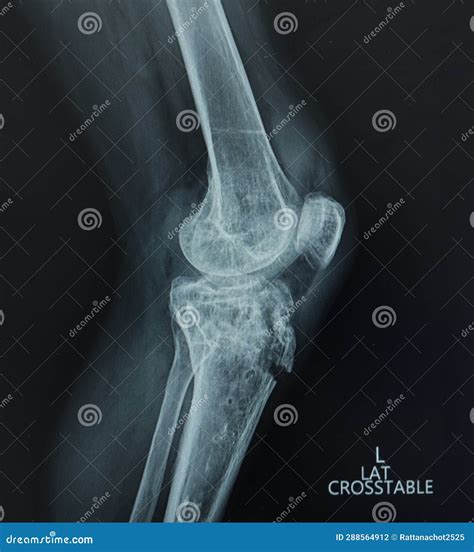

A Lateral Knee Xray is a type of radiographic imaging that captures a side view of the knee joint. This view is essential for evaluating the alignment of the bones, the condition of the joint spaces, and the presence of any abnormalities such as fractures, dislocations, or arthritis. The lateral view complements other views, such as the anteroposterior (AP) and oblique views, to provide a comprehensive assessment of the knee.

• Evaluating Joint Spaces: It provides a clear view of the joint spaces, which can indicate the presence of arthritis or other degenerative conditions.

• Arthritis: Joint space narrowing and bone spurs can indicate osteoarthritis or other forms of arthritis.

• Patellar Dislocation: Misalignment of the patella can be diagnosed with a lateral view.

• Tibial Plateau Fracture: This type of fracture, which involves the upper part of the tibia, can be clearly seen in a lateral view.